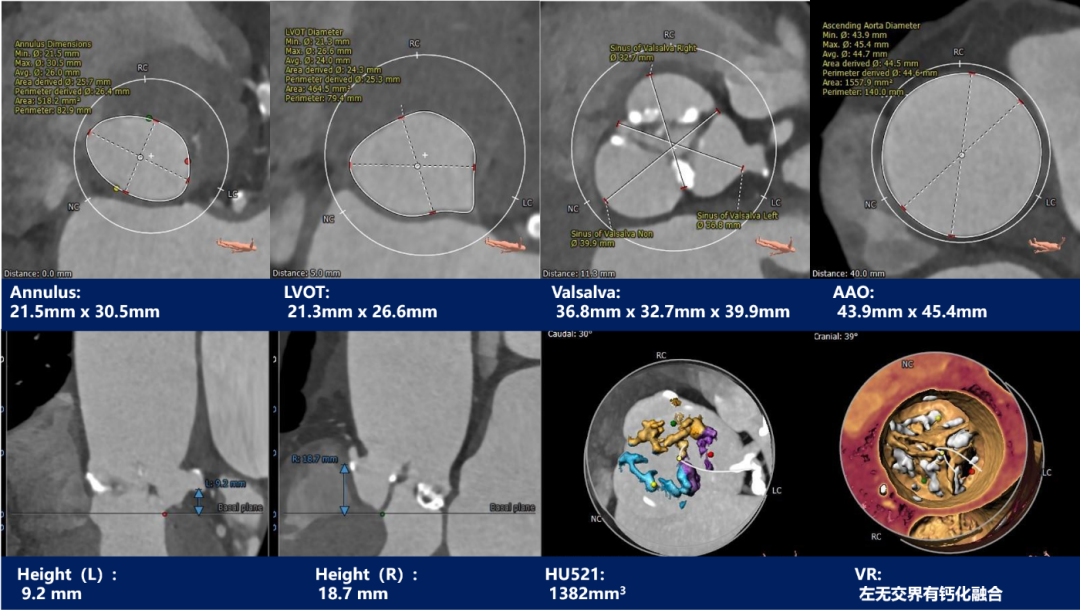

主动脉根部测量

CT特点:三叶式主动脉瓣,左右窦发育较无冠窦小;左冠开口高度低,右冠高度可,左右冠起始处可见钙化及病变,右冠瓣长度>冠脉开口与瓣叶附着缘距离;左室流出道内径稍小于瓣环径,瓦氏窦内径宽,窦管交界及升主动脉扩张。

瓣上测量

瓣上测量:中度钙化,左无交界有钙化融合,瓣叶中度钙化并纤维增厚,钙化分布较均匀,仅左无交界呈团块样。